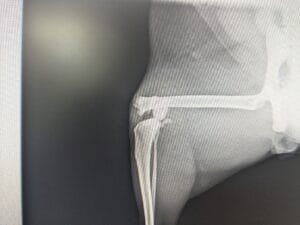

犬の中手骨・中足骨骨折について|症例をもとに治療法と注意点を解説中手骨/中足骨骨折

骨折しやすい手の甲・足の甲部分である中手骨・中足骨に起こる骨折。今回はその分類「中手骨/中足骨骨折」の症例をもとに、治療の流れと術後のケアをわかりやすく解説します。